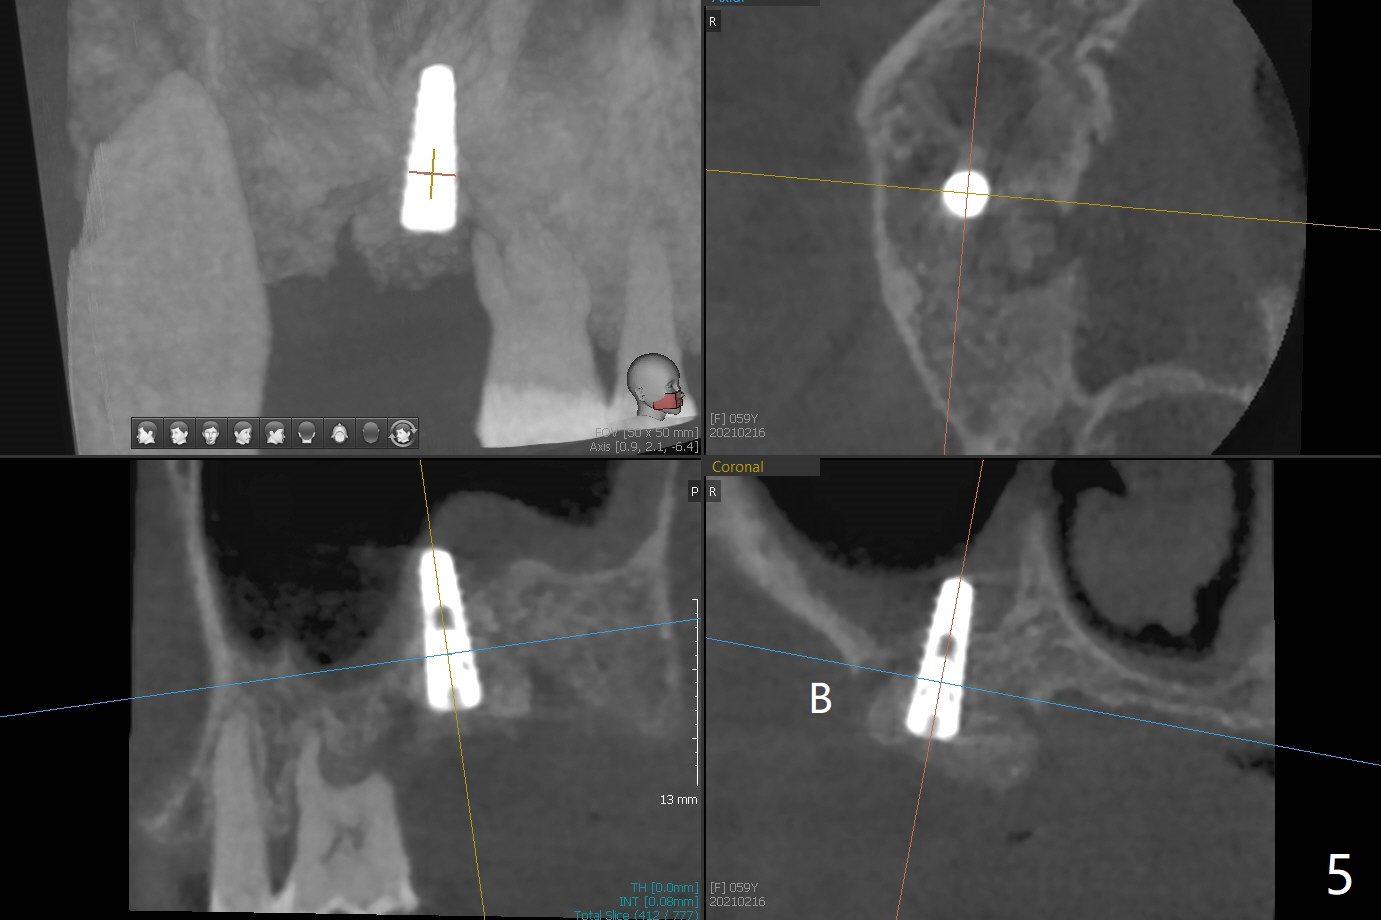

The offset is the distance from metal sleeve top to the fixture top (Fig.1). There are 3 kinds of offset options, 9 (standard), 10.5, and 12mm.When we raise the level of metal sleeve top from the soft tissue, then we’ll have more space between the metal sleeve top and the fixture top which means your bone trimmer & osteotomy drills need to be longer to compensate the vertical difference. 为了减轻张口度问题,预备两个导板,先用9毫米补偿导板(图二(理论上偏移会少些)):从2.2x7.3至3.0x10毫米钻头,但是插入3.0x11.5毫米钻头就有困难,所以接着使用6毫米补偿导板(图三)和3.0x8.5毫米钻头完成钻洞。不过又使用前个导板放置3.5x11.5毫米IS报废植体,扭力很低,用手指旋入,不假思索放置最终植体(4x11毫米),扭力仍低,增加植入深度接近3毫米,扭力没有明显提高,但是还稳定,不过放置修复基台,植体好像松动,只好取出,放置愈合帽。虽然植体植入太深些,但是有利于颊侧骨粉血供,因为颊侧牙龈明显退缩,植体稍微龈下,离颊侧牙龈大约3毫米。放置Vanilla粘性骨粉,两张PRF膜,以及树脂敷料。术后即刻根尖片显示植体似乎种得太深了(图四),不得不拍摄小范畴CT,原来植体往颊侧偏移,并且植入上颌窦(图五)。术后几小时没有鼻出血。术后一周复查正常。撤去树脂敷料后,重新插入导板,检查是否完全就位。一般树脂敷料撤除需要用手机切开,这次利用敷料薄,有一定弹性,一下子就把取出(图六)。敷料内侧是凹陷的(图七:*),说明手术时伤口放置过量PRF膜,但是术后一个月,伤口却是凹陷(图八(暴露愈合帽)),说明PRF溶解,骨粉遗失?少量骨粉附着于牙龈袖上。颊侧牙龈萎缩减轻了。